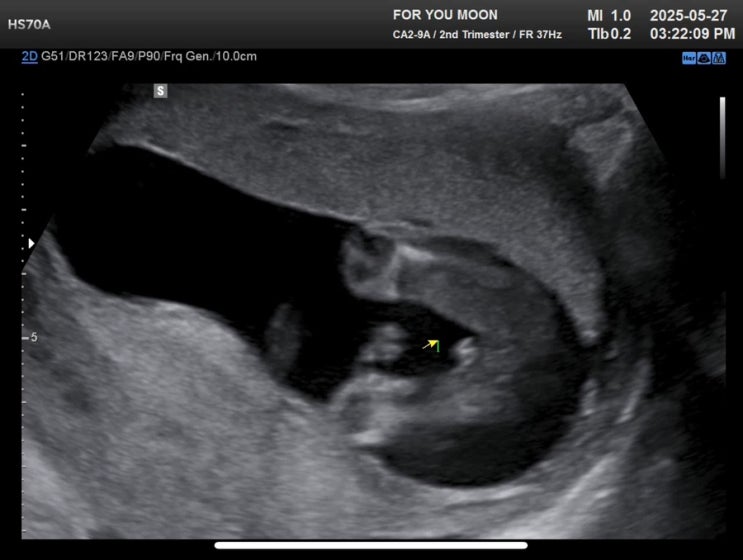

포유문 산부인과 입체초음파 가격 후기, 임당 검사

26주에 진행하는 임신성 당뇨 검사! 포유문 산부인과는 임신성 당뇨 검사 날에 입체초음파도 함께 볼 수 있...